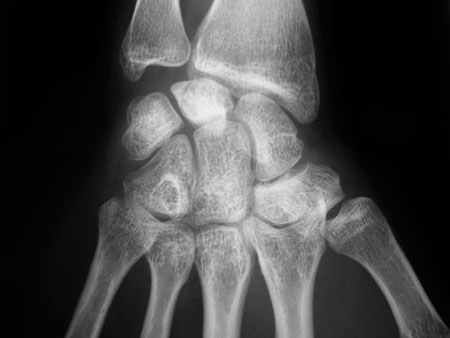

Technique Ostéotomie du capitatum et nécrose du lunatum dans la maladie de Kienbock , Fabrice Rabarin Centre de la main, Village santé Angers Loire, 47 rue de la Foucaudière 49800 Trelaze, France 🖂 rabarin@centredelamain.fr , Bruno Cesari Centre de la Main, 2 rue Auguste Gautier, Angers, France 🖂 cdm@unimedia.fr , Yann Saint Cast Centre de la Main, 2 rue Auguste Gautier, Angers, France , Pierre-Alain Fouque Centre de la Main, 2 rue Auguste Gautier, Angers, France , Guy Raimbeau Centre de la Main, 2 rue Auguste Gautier, Angers, France 🖂 cdm@unimedia.fr N°179 - Décembre 2008 ● 7 min de lecture